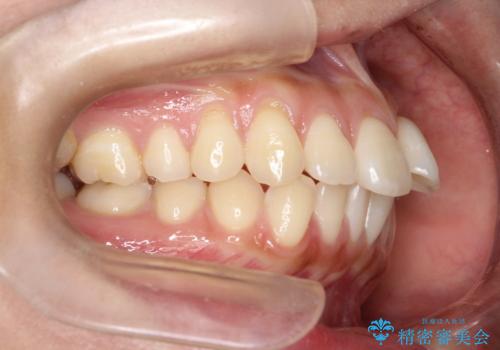

- 矯正装置

- 審美装置

- 前歯の凸凹を主訴に来院されました。

予想治療期間2年でしたが、実際は1年半ほどで終了し満足していただきました。

小臼歯抜歯(上顎4番)して矯正治療を行なったことで、口元もスッキリしました。